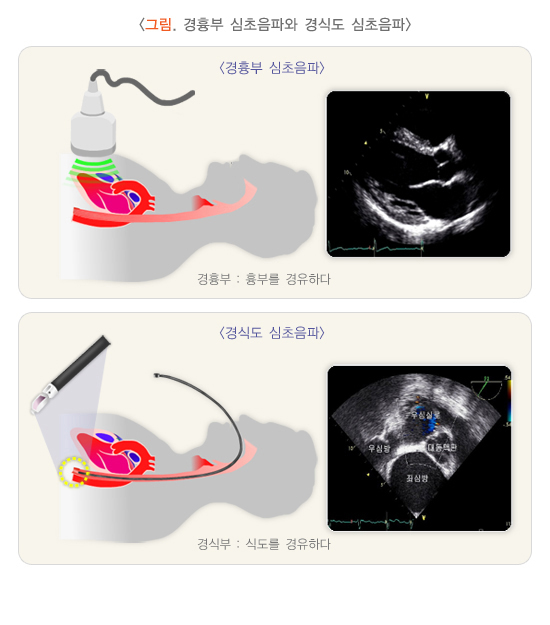

- 심장 초음파 검사

- 경흉부 심장초음파는 별도의 금식이나 준비가 필요 없으며, 검사복으로 갈아입고 검사합니다.

- 경식도 심장초음파나 약물부하 심장초음파는 검사 전 금식 및 약 복용 관련 별도의 지시가 있을 수 있습니다.